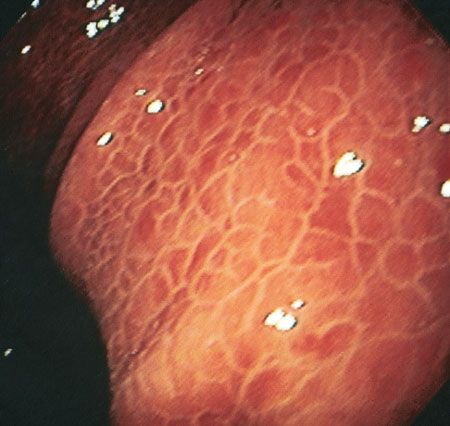

This endoscopic view shows the stomach of a 52-year-old man with a history of chronic hepatitis C and alcohol abuse who was hospitalized because of bleeding esophageal varices. Seen is the classic macroscopic “snakeskin” appearance of portal hypertensive gastropathy-a fine reticular pattern that separates areas of erythematous mucosa. Histological examination disclosed extensive edema and submucosal vessel dilation.